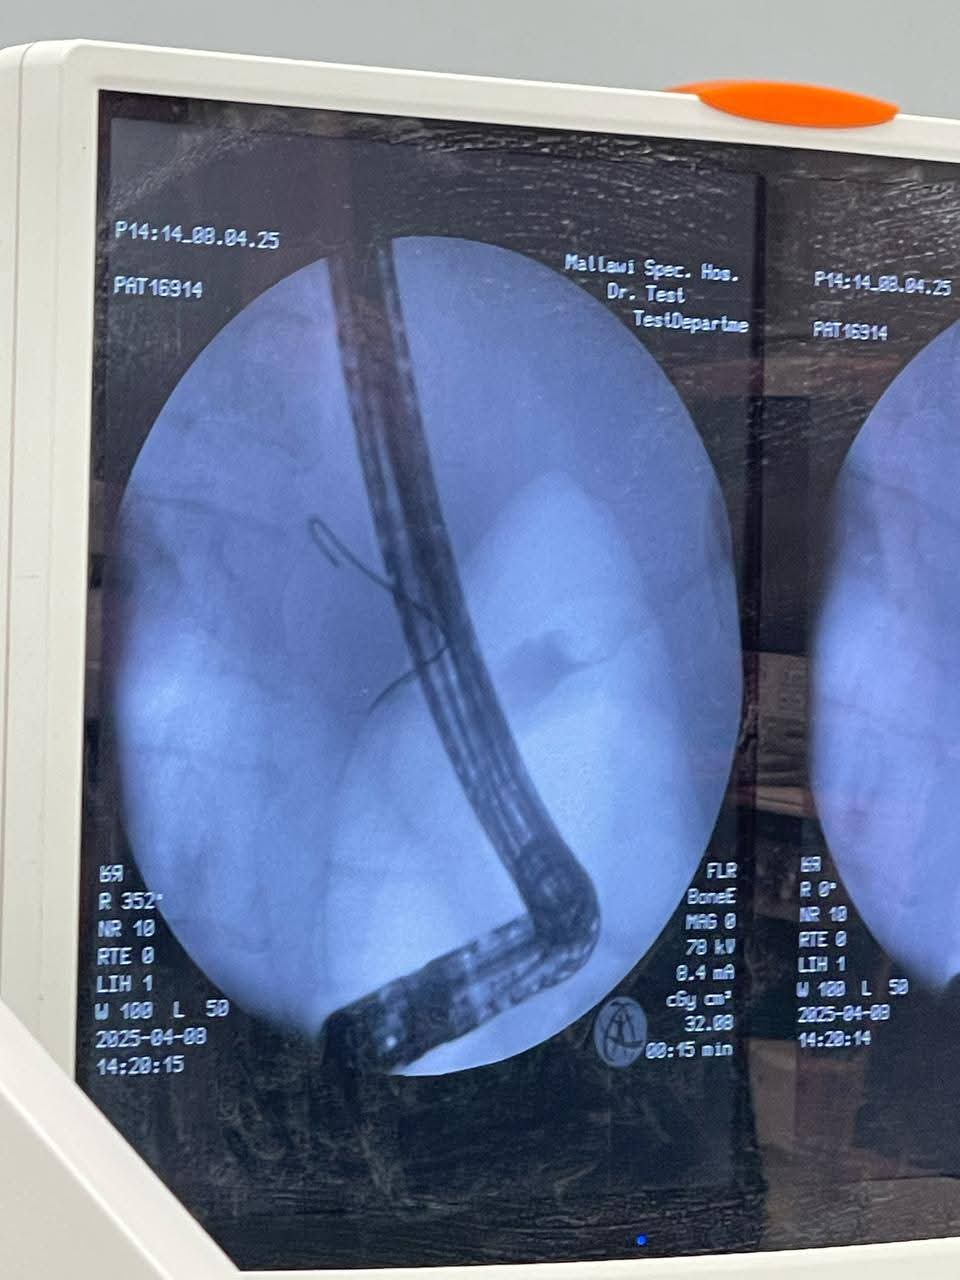

حقق فريق العمل في قسم الجهاز الهضمي والمناظير في مستشفى ملوي التخصصي نجاحًا كبيرًا اليوم ، بعد إجراء 6 مناظير لقنوات مرارية، حيث استقبلت الوحدة ثلاث حالات مرضية بتدرجات مختلفة من الصعوبة.

الحالة الأولى، كانت لمريضة تبلغ من العمر 67 عامًا تعاني من التهاب شديد في المرارة، بالإضافة إلى انسداد جزئي في القنوات المرارية بسبب وجود حصوات عديدة، تم تركيب دعامة وتسليك القنوات المرارية بنجاح.

أما الحالة الثانية، فكانت لمسنة تبلغ 75 عامًا تعاني من انسداد كامل في القنوات المرارية نتيجة ورم سرطاني، وقد تم إجراء توسيع للقنوات وتركيب دعامة لتسهيل تدفق الصفراء.

فيما تم التعامل مع الحالة الثالثة، لمريض يبلغ من العمر 77 عامًا، حيث استُبدلت دعامة في القنوات المرارية بسبب انسداد مراري بالدعامة الموجودة، مما تسبب في ضيق القنوات.

وقدم الدكتور أحمد عمر مدير مستشفى ملوي التخصصي الشكر لفريق جراحات الجهاز الهضمي، بقيادة الأستاذ الدكتور أحمد صادق، استشاري جراحة المناظير، والدكتور بهجت كمال، استشاري الجهاز الهضمي والمناظير، بالإضافة إلى فريق التخدير الذي ضم الدكتور أحمد سعد والدكتور محمد مختار، وفريق التمريض والفنيين في العمليات.